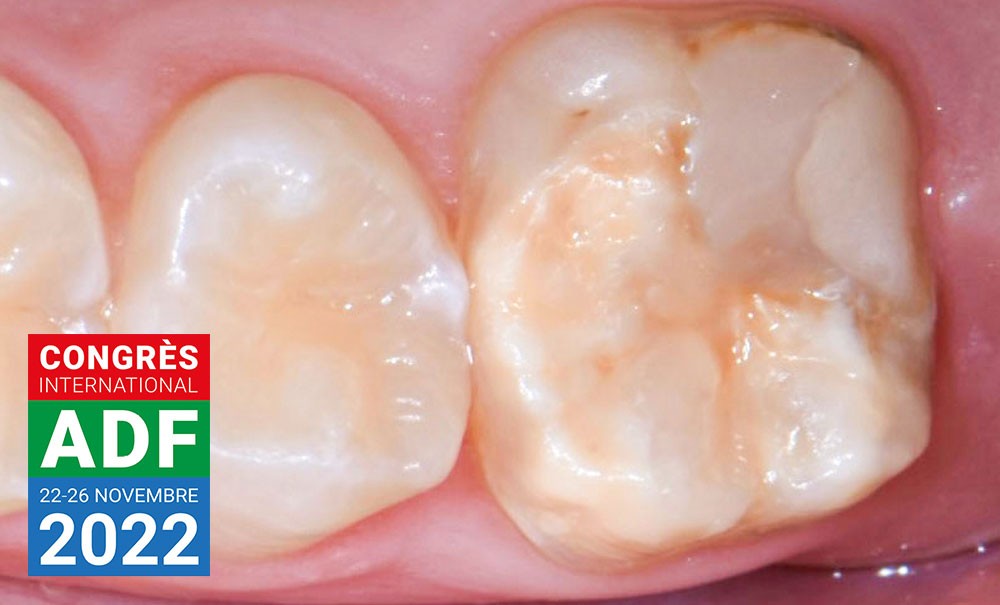

Est-il possible de coller un onlay sur une dent temporaire ?

Élisabeth Dursun : En cas de perte de substance importante sur molaire temporaire, il est classiquement réalisé une coiffe pédiatrique préformée : thérapeutique fiable et simple…